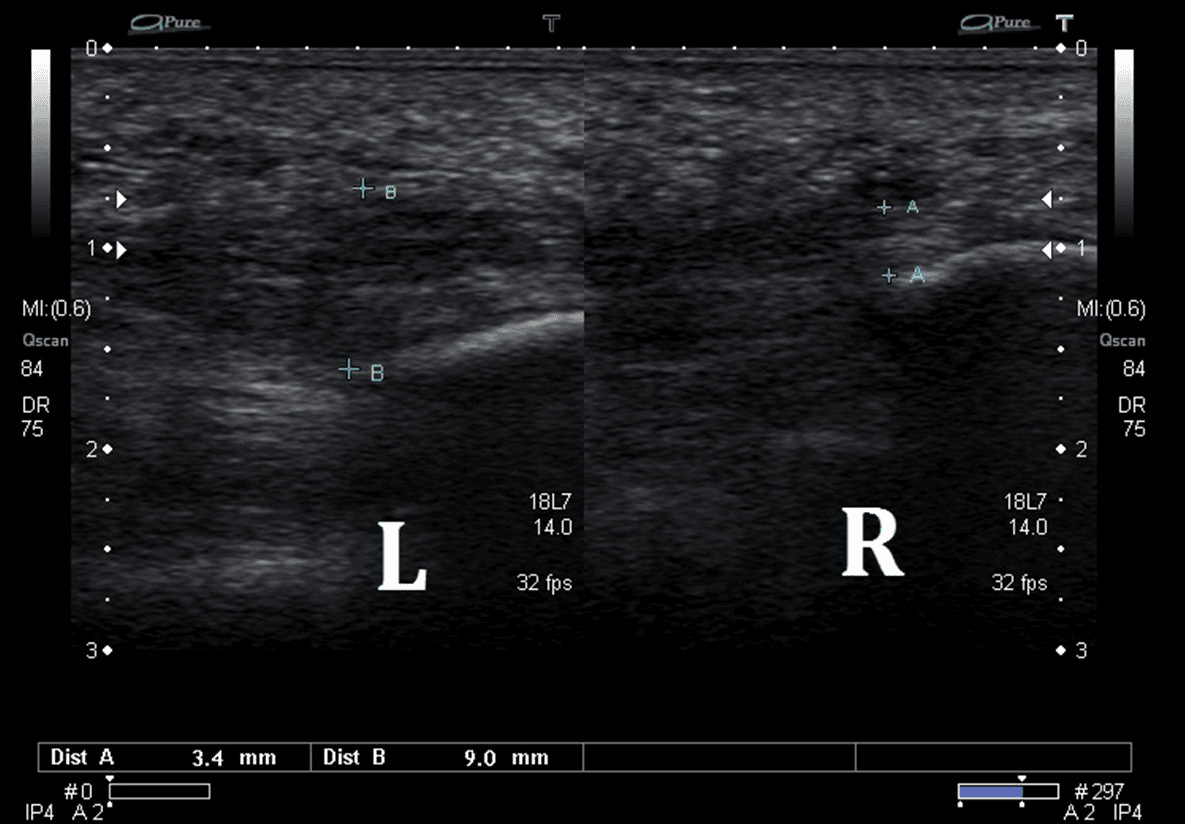

Plantar Wart Ultrasound . ( a ) greyscale and ( b ) color doppler demonstrate fusiform shaped, hypoechoic, epidermal and dermal structure. Note the central echogenic punctum. Sonography may be considered as reliable support for plantar wart diagnosis and may have a role in the evaluation of plantar wart treatment modalities, allowing monitoring of therapeutic responses, especially in recurrent and difficult cases with persistent symptoms such as pain. These are lesions produced by human papillomavirus. The diagnosis is primarily clinical but may be seen as a hypoechoic lesions lying subdermally along the. Plantar warts, or verrucae plantaris, are cutaneous lesions on the plantar aspect of the foot that are caused by the infection of. On ultrasound, they show as hypoechoic fusiform epidermal and dermal. Plantar warts commonly present underlying bursitis. Typical small, focal thickening of the skin and subcutaneous tissues with dramatic increase in vascularity. On color doppler, variable degrees of vascularity (from hypovascular to.

Plantar wart (left foot). (A) Gray scale shows hypoechoic fusiform Plantar Wart Ultrasound Note the central echogenic punctum. Plantar warts, or verrucae plantaris, are cutaneous lesions on the plantar aspect of the foot that are caused by the infection of. ( a ) greyscale and ( b ) color doppler demonstrate fusiform shaped, hypoechoic, epidermal and dermal structure. The diagnosis is primarily clinical but may be seen as a hypoechoic lesions lying subdermally. Plantar Wart Ultrasound.